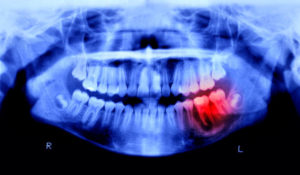

親知らずの正式名称は、第3大臼歯と言い、口腔内の一番奥にある歯を指します。親知らずという呼び方は「親の手を離れて知らない間に生えている歯」という意味が語源になっています。親知らずは年齢で言うと、一般的には18歳〜22歳頃に生えてくることが多く、向きや形が個人差がある為、磨き残しが発生しやすいです。上手に磨くことが出来ないとそこに細菌が繁殖し虫歯の原因になることも考えられます。日本人は特にアゴが小さい傾向もある為、親知らずが極端に斜めに生えてしまう可能性も十分に考えられます。親知らずの抜歯をするか検討している方は、是非この記事を参考にしてみて下さい。

親知らずを抜歯する手法は様々あります。歯茎を切開して、中に沈んでしまった親知らずを砕きながら抜いたりする場合もあります。場合によっては周囲の骨を削りながら手術をすることもあります。抜歯をする際は、少なからず部分的に麻酔をして手術をするため、患者様によって状況が異なりますが顔が晴れることは往々にしてあります。腫れる人の中でも周囲が見てすぐに気づくような方は、口腔内の環境が元々あまり良くなかった可能性もあります。それは、口腔内の環境が悪いと抜歯をした後にその傷口から細菌が侵入し炎症へ繋がる場合があるからです。基本的には歯科医師は手術に慣れている為、それほど顔が腫れる場合は少ないですが、患者本人の口腔内の状況や体調にも左右される為、施術の前などは食事や睡眠などにしっかりと気を配り、心身共に健康な状態で当日を迎えることをお勧め致します。